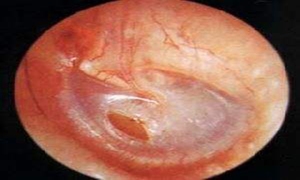

早期可见鼓膜轻度充血、内陷,若中耳有积液,则可在鼓膜上见到液平面,或见鼓膜外突。若反复发作,可见鼓膜增厚凹陷,或见灰白色斑块,或萎缩、疤痕粘连。听力检查呈传导性耳聋,反复发作者可呈混合性耳聋。声导抗检查呈B型或C型鼓室导抗图。